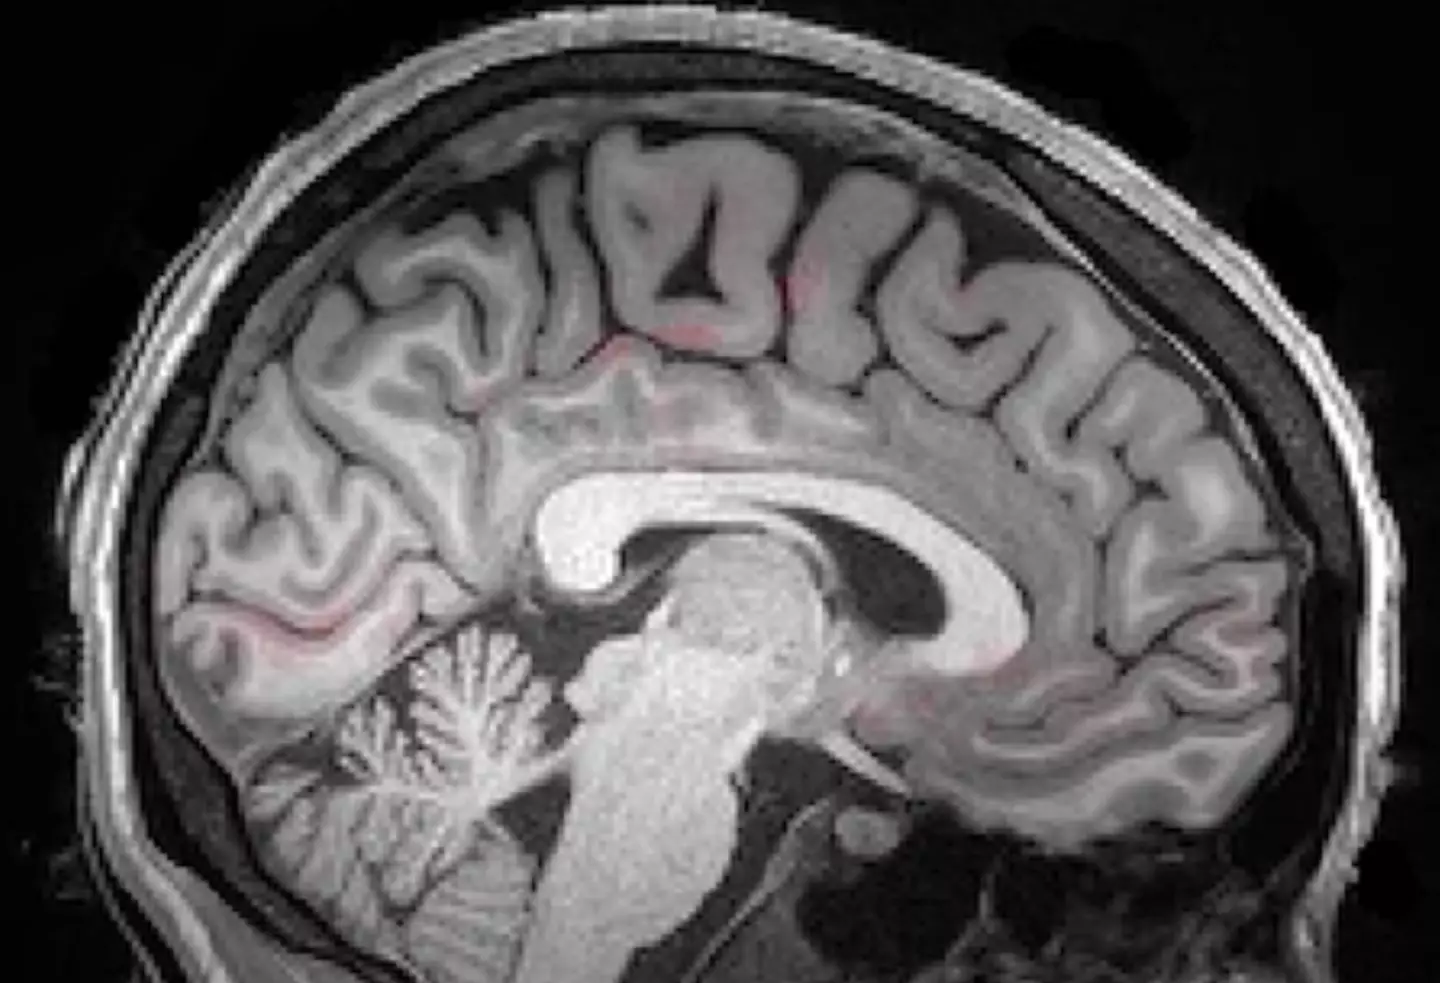

For the study, 13 people aged between 23-33 were recruited to lie inside an MRI machine and go to sleep.

The MRI machine then captured images of the participants' brains' CSF.

And the images revealed your brain is a lot more active than you may realize when you rest your head on your pillow and attempt to nod off and get your eight hours.